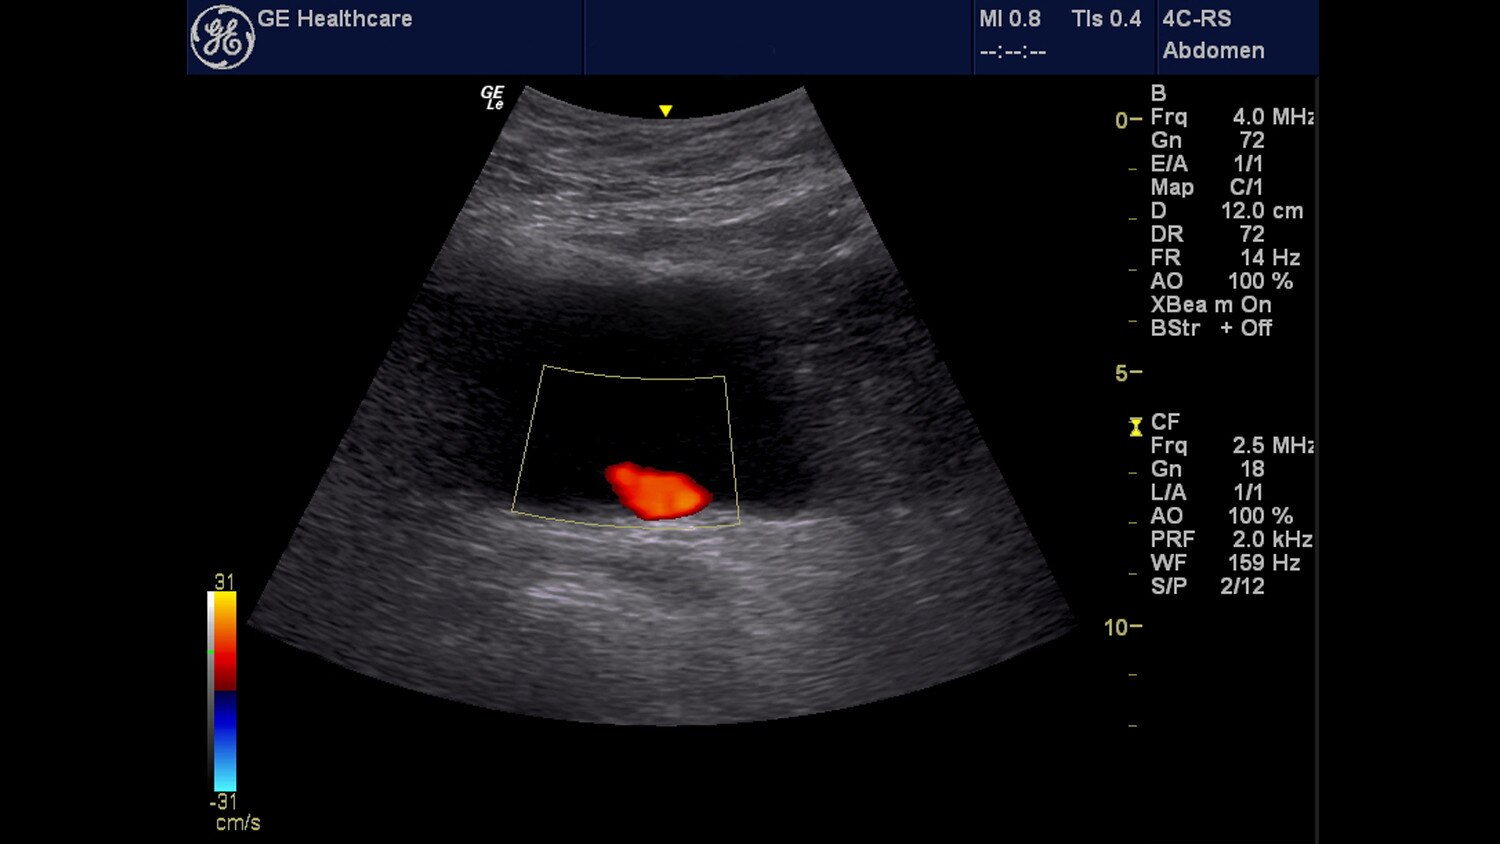

We are pleased to welcome you to GE's dedicated ultrasound website for emergency medicine!

We want to make it simple for you to access clinically relevant information that can help you successfully incorporate ultrasound into your practice or continue your search for topics to help advance your knowledge. This is a site designed specifically for you, the emergency medicine physician, to provide one-stop access to ultrasound information.